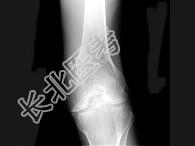

- 单项选择题男,38岁, 左膝痛,受伤时出血较多, 结合图像,最可能的诊断是 ( )

A、白血病

B、血友病性关节炎

C、骨巨细胞瘤

D、退行性骨关节病

E、类风湿关节炎